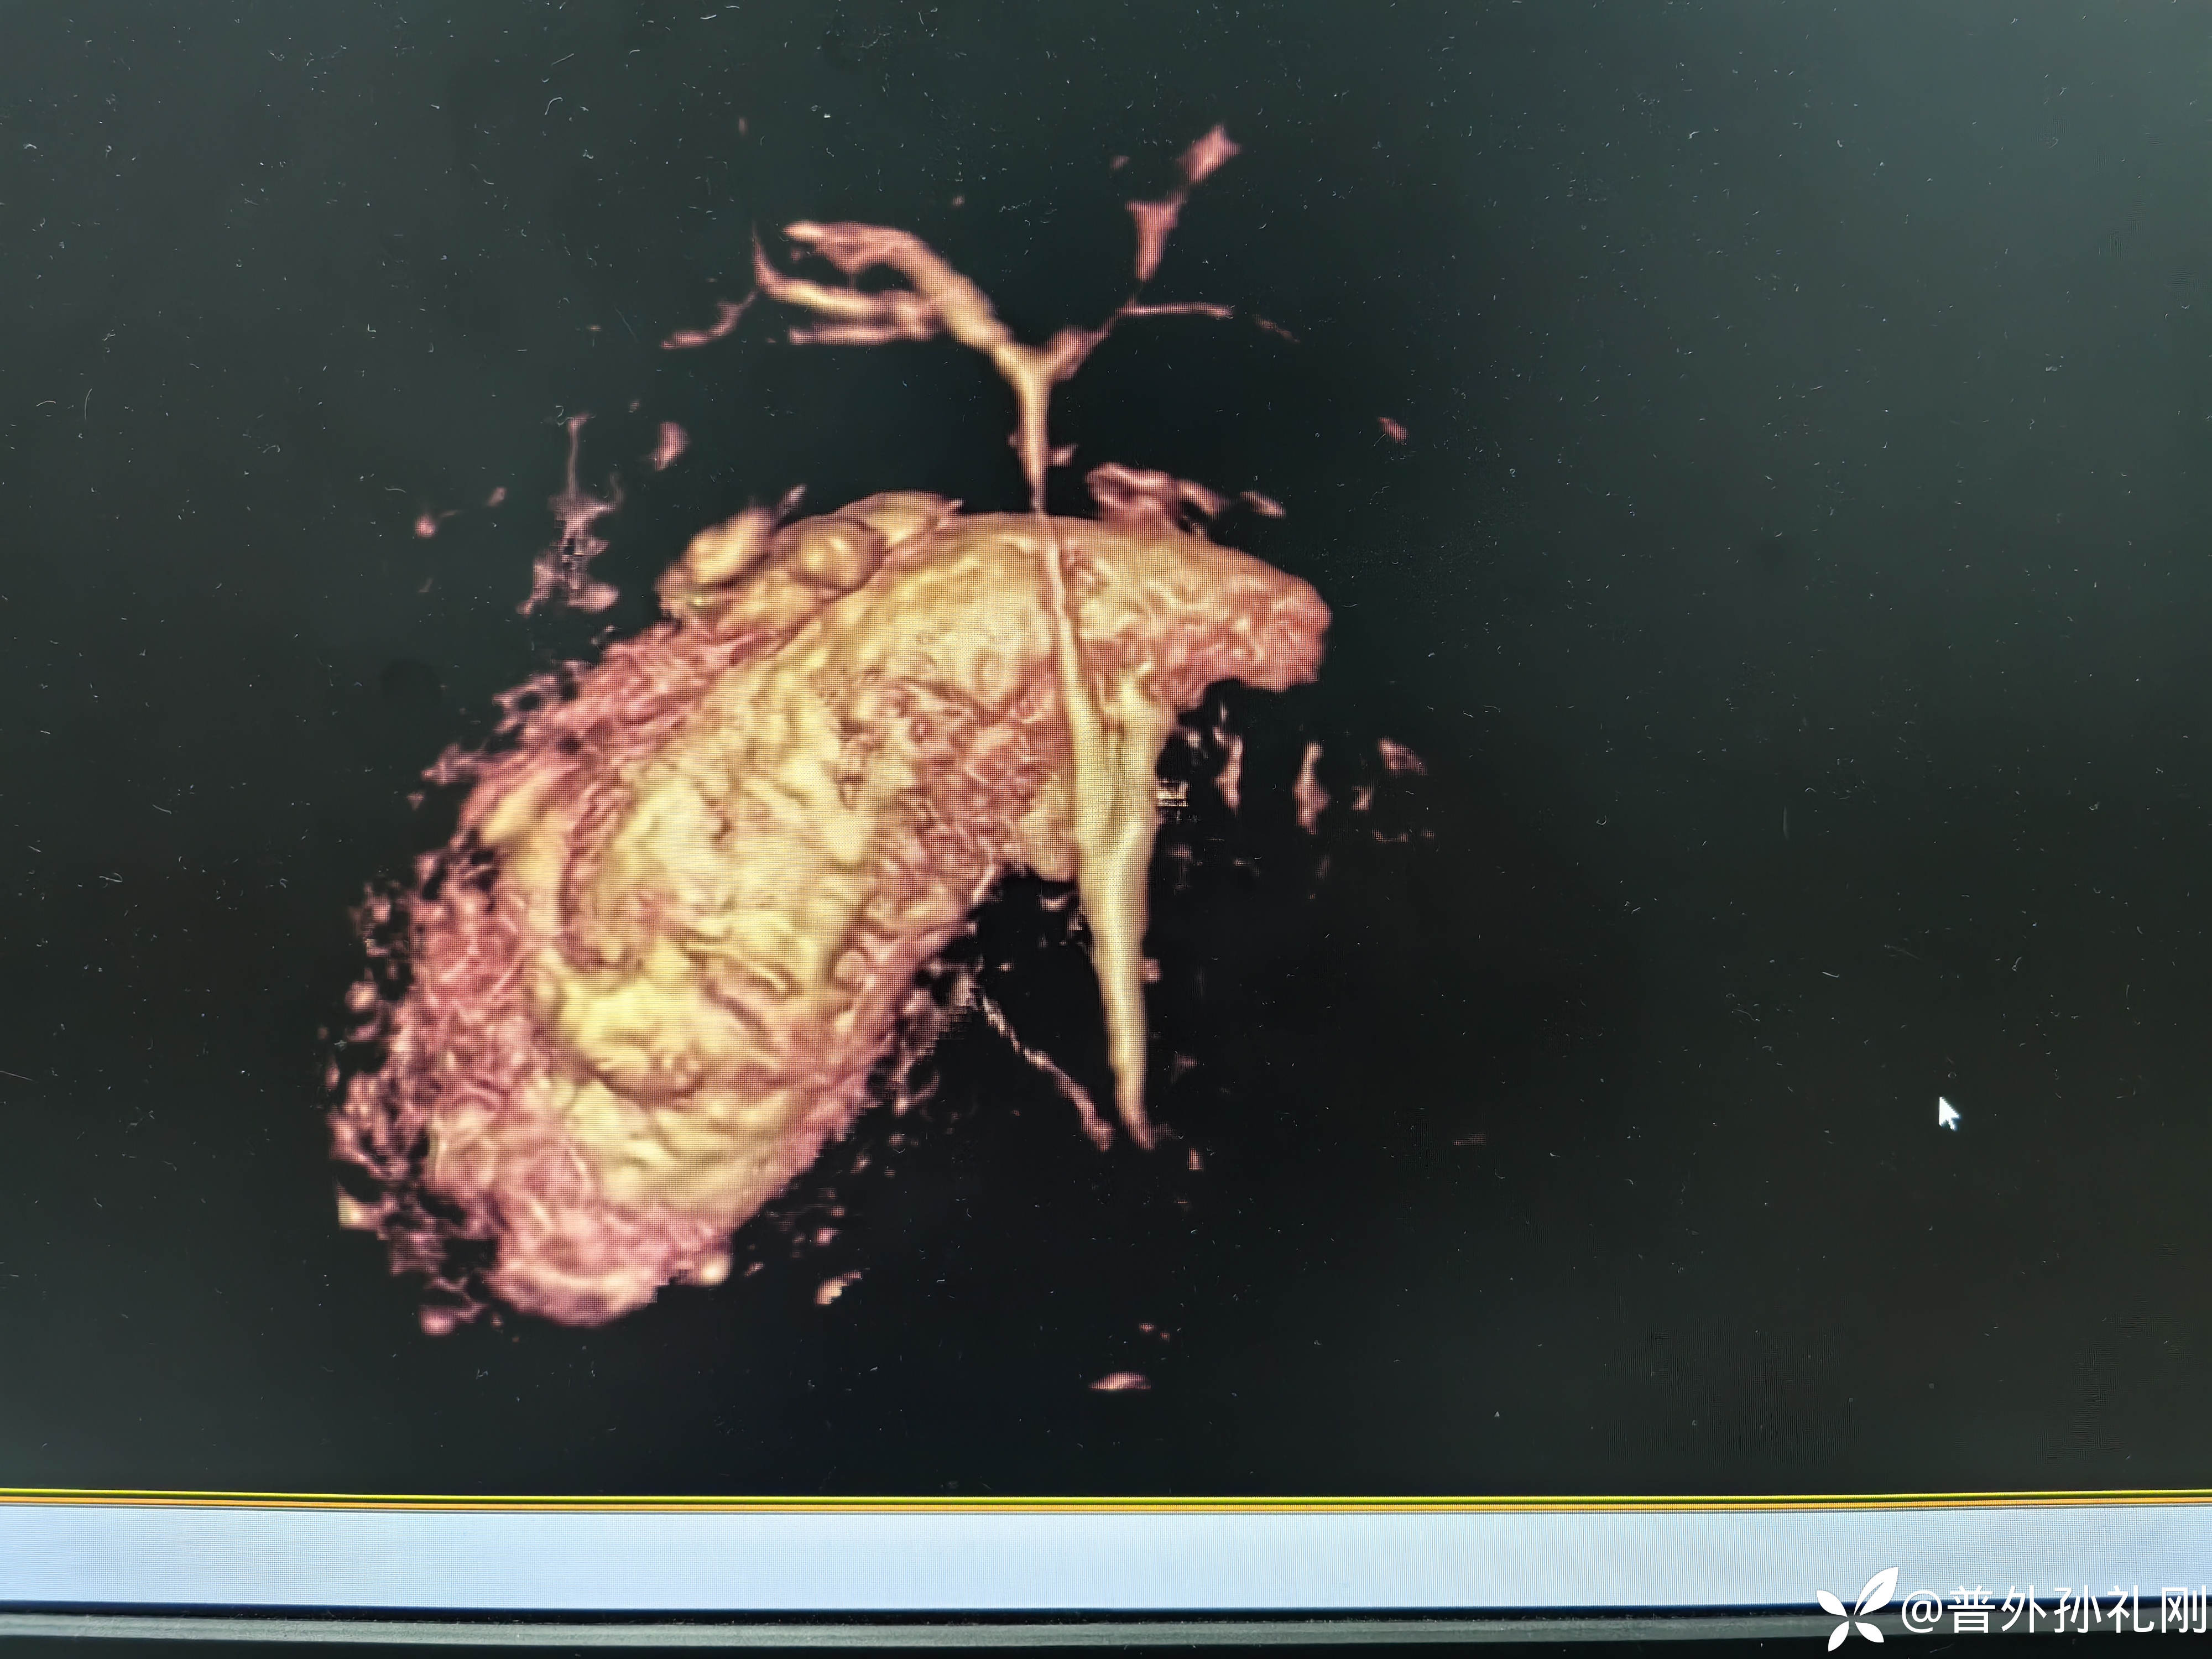

MRCP三维成像后面观:胆总管(肝总管)直径细小,胆囊管直径比胆总管直径要粗(图像上左侧短而粗的管道为胆囊管、图像上右侧细长的管道为胆总管(肝总管))

这张图片可以看出胆囊管位于胆总管后方,从后方汇入胆总管,且胆囊管直径明显比胆总管直径要粗

这张三位成像更加清晰明了,胆总管直径要短于胆囊管

虽然胆总管直径较细,但是至少可以排除胆总管结石的可能了,当然,这么细的胆总管,一旦发生损伤,后果也可能是灾难性的。